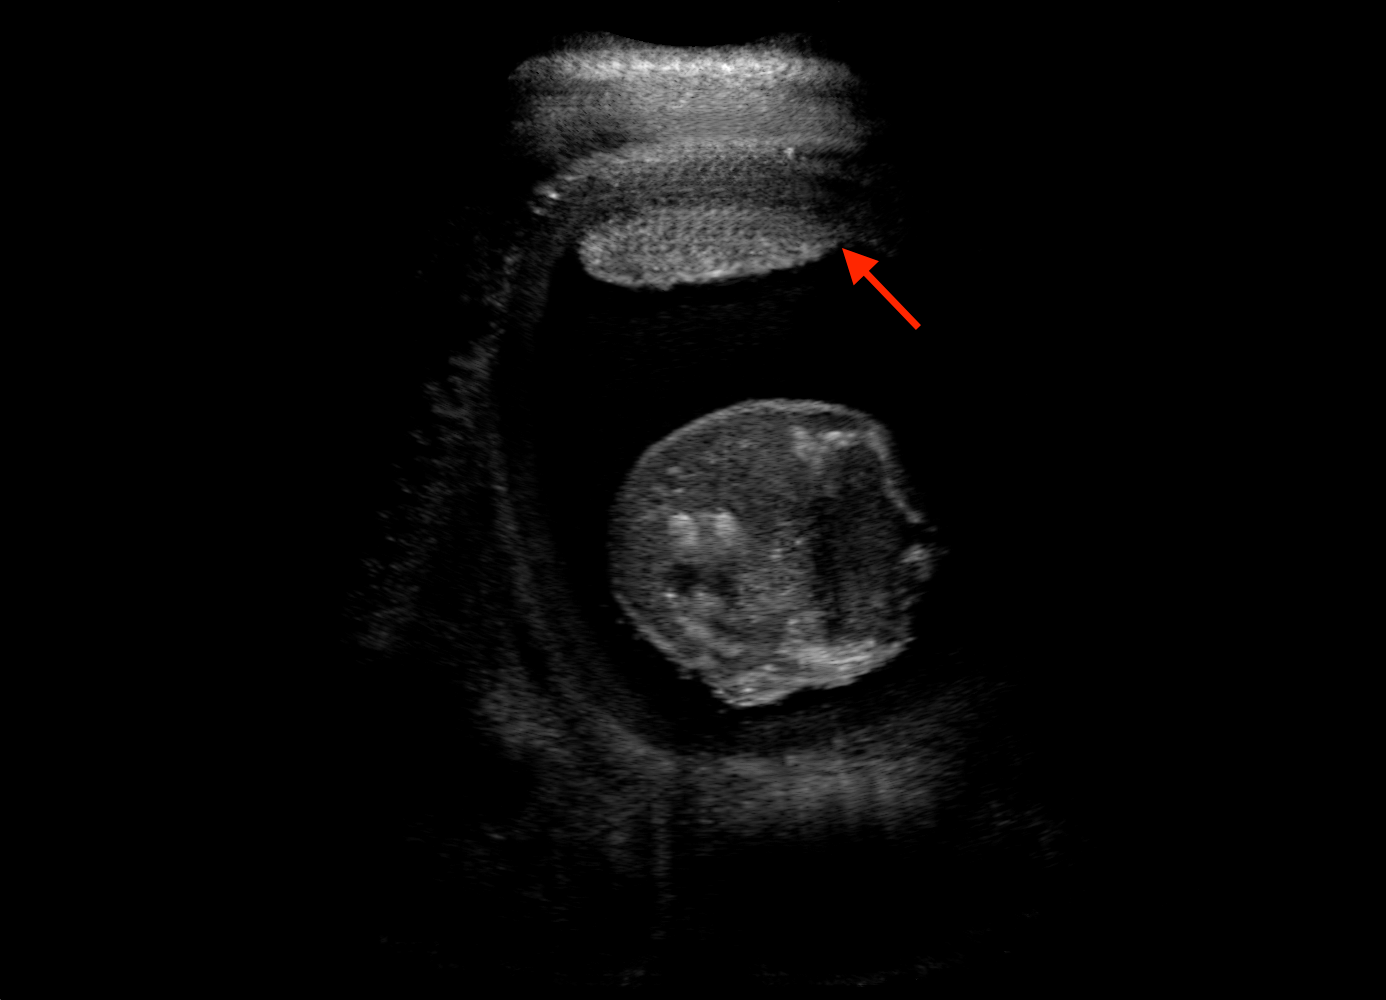

For the interpretation of the local errors, sample spatial p error maps are depicted in Fig. 3 for LSA2H, NSA2H, and SA2H for the middle two examples shown in Fig. 2. Both images generated by NSA2H have a lot of missing structures and accordingly have high error almost all over the map. Artificial skull enhancement with LSA2H is seem to evoke large p error, as shown in the corresponding error map, whereas the bright spots in the error map of SA2H reflect some hallucinated shadows and structure in the brain. All of above mentioned regions of interest are marked by red arrows. In the bottom example, SA2H fails to generate faithful content at the bottom region marked by red circles, which is well indicated by the error map as well.